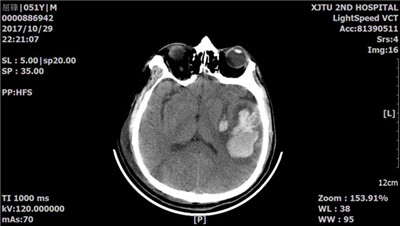

经积极的肺保护通气策略及有效的抗炎、抗感染、循环支持等治疗,患者病情一度好转。但随后却出现意识障碍进行性加重及右侧偏瘫症状!复查头颅CT,见左侧颞叶大面积脑出血(图3)。

图3:头颅CT示脑脓肿并出血